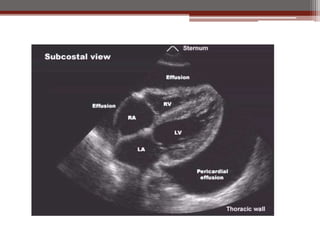

Ecocardiograma

Punción

Pericárdica

Ecocardiograma 1. Estudio máseficaz para derrame pericárdico 2. Permite identificar cardiomegalia por dilatación de cavidades o derrame pericárdico. 3. Cantidad de derrame